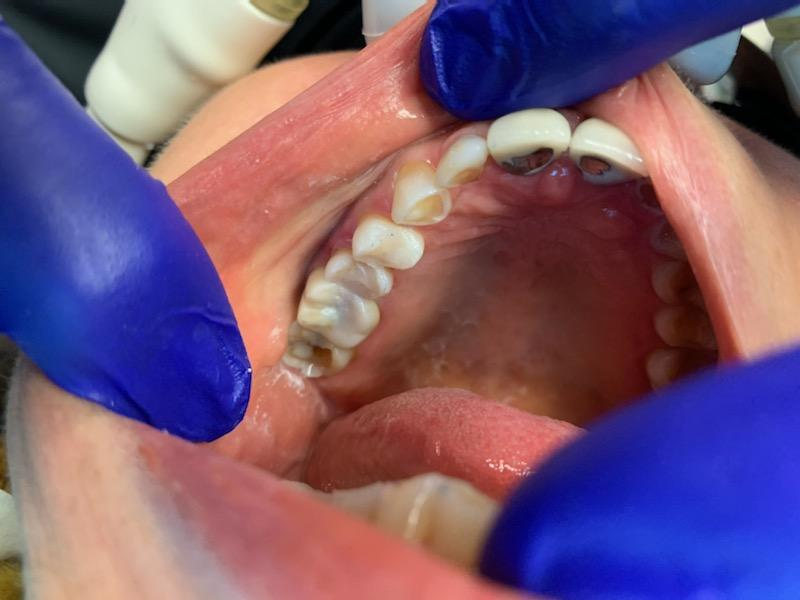

2

Anterior broken tooth. Double DentXpinTM repair.

3